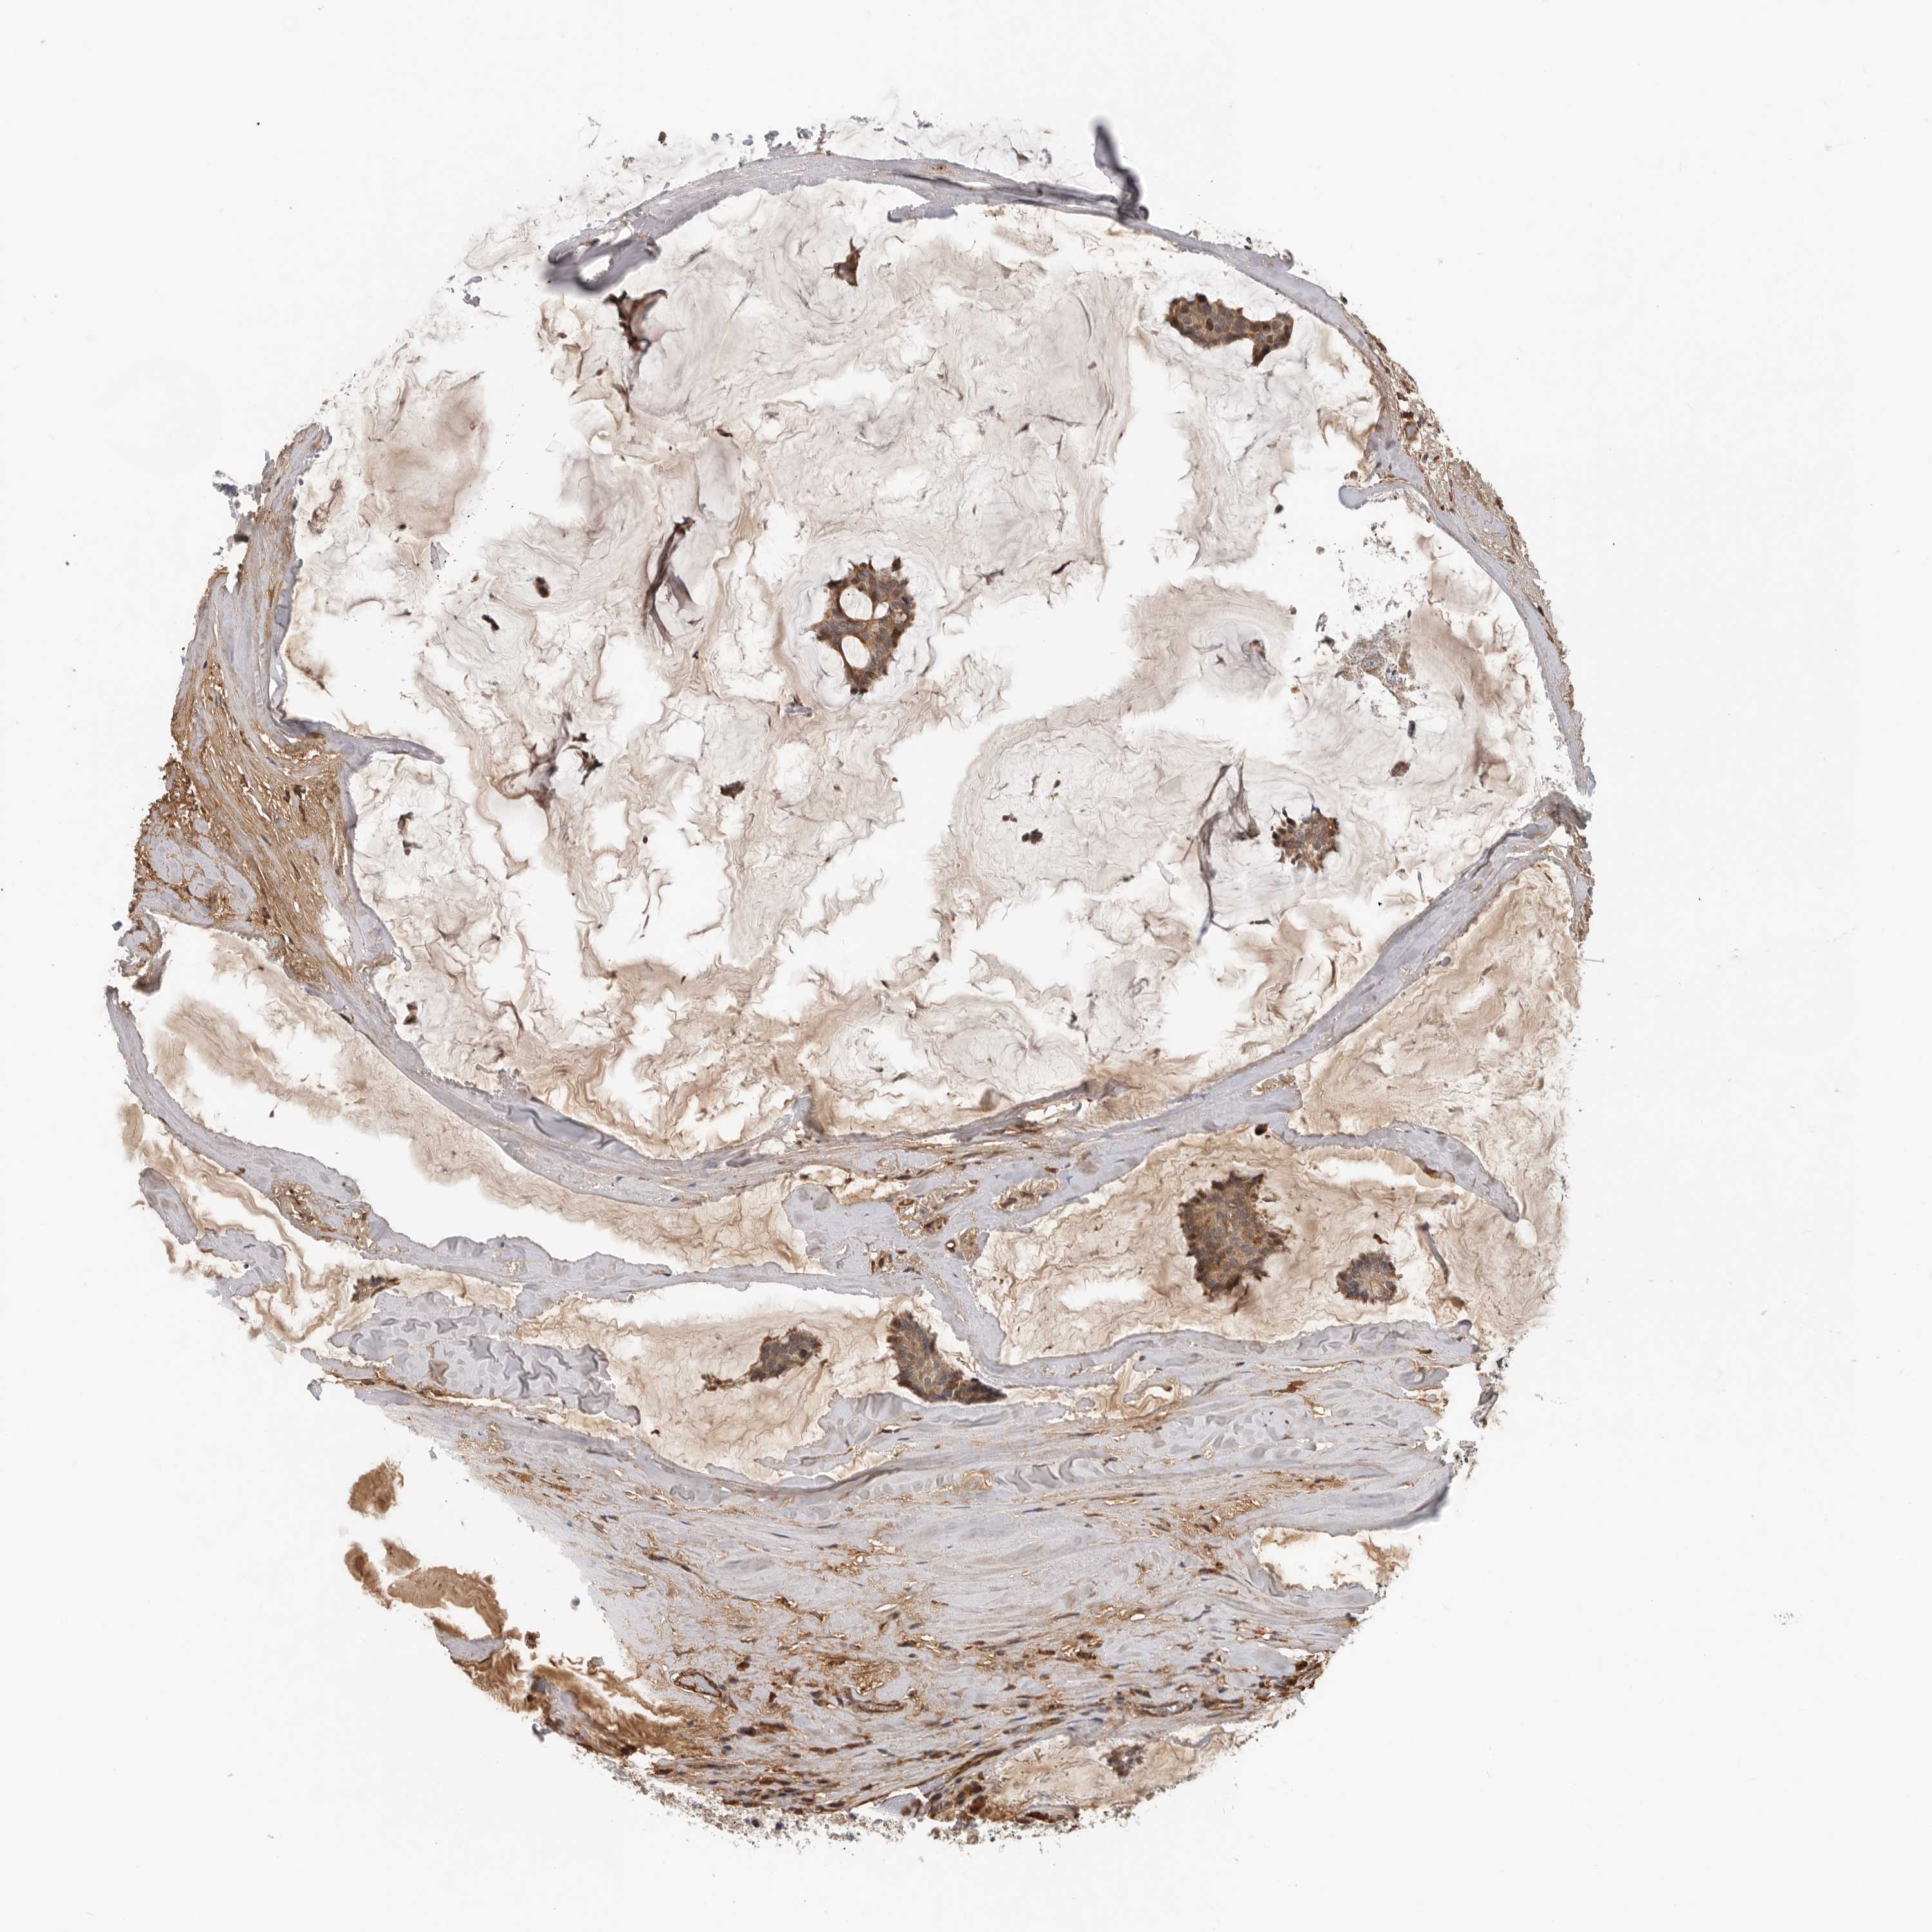

CANCER BREAST CANCER Show tissue menu

BRCA TCGA BRCA VALIDATION PROTEIN EXPRESSION